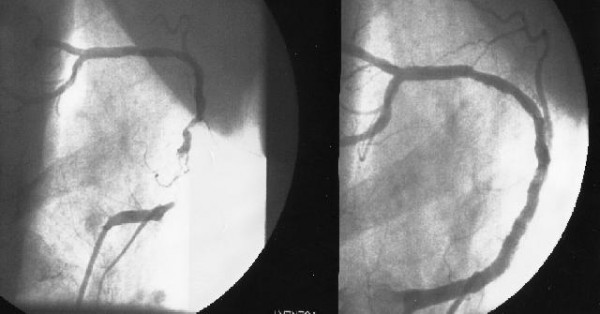

Radios de mon artère coronaire droite, avant et après installation de deux stents sur 4cm (OSHKOSH, 29 JUILLET 2005)